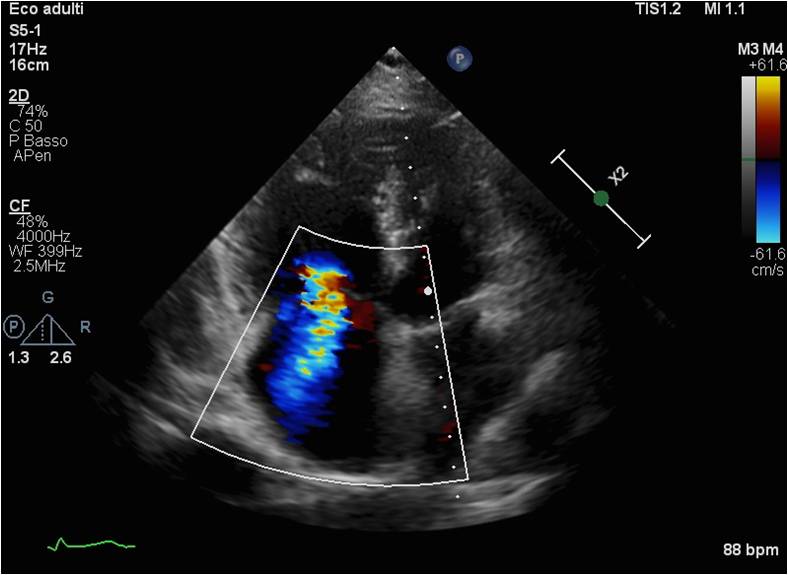

Introduction Idiopathic pulmonary arterial hypertension (IPAH) is a rare and progressive disease characterized by elevated pulmonary arterial pressure in the absence of identifiable causes, leading to increased vascular resistance and right ventricular overload. Early diagnosis and targeted therapy are critical for improving prognosis (1). Clinical case A 46-year-old female came to our attention for worsening episodes of syncope and dyspnea (NYHA III). Echocardiogram revealed moderate tricuspid regurgitation, PAPs 108 mmHg, right heart dilation, TAPSE 16 mm, atrial septal aneurysm and suspected patent foramen ovale (PFO). A dynamic test for right-to-left shunt revealed a mild shunt. NT-proBNP was 680 pg/ml. Myocardial perfusion imaging, spirometry, abdominal ultrasound, HIV tests, autoimmune panel and videocapillaroscopy were normal. Ventilation-perfusion scintigraphy showed areas of hypoperfusion but computerized tomography excluded thromboembolic form. Right heart catheterization showed a mean pulmonary pressure of 48 mmHg, a wedge pressure of 10 mmHg and vascular resistances (PVR) of 12.2 WU. According to ESC guidelines PFO wasn’t closed and, given the high PVR, we concluded with a diagnosis of IPAH with incidental finding of PFO. During 6-minute walk test (6MWT) the patient covered 320 meters with desaturation. This was integrated with NT-proBNP, clinical, echocardiographic (TAPSE/PAPs 0.16, RA area 19 cm², absence of pericardial effusion) and hemodynamic parameters (RAP 6 mmHg, CI 1.8 L/min/m², SVI 20 mL/m²), concluding with an intermediate risk. We opted for an upfront combination therapy. The patient showed significant improvement in NYHA class (I-II) and no more syncope. NT-proBNP was reduced to 265 pg/ml and she covered 452 meters without desaturation. The patient's risk profile had dropped to low risk. However, she still had PAPs of 65 mmHg and needed a major bilateral hystero-oophorectomy so we added a third drug with subsequent substantial reduction in PAPs. Conclusion In these high-risk patients we must not limit ourselves to NYHA class and functional capacity. Guidelines state that PAH patients are at high risk of right heart failure and death. Therefore they recommend therapeutic optimization before surgery. References Humbert M, Kovacs G, Hoeper MM, et al. 2022 ESC/ERS guidelines for the diagnosis and treatment of pulmonary hypertension. Eur Heart J. 2022 Oct 11;43 (38):3618-731.